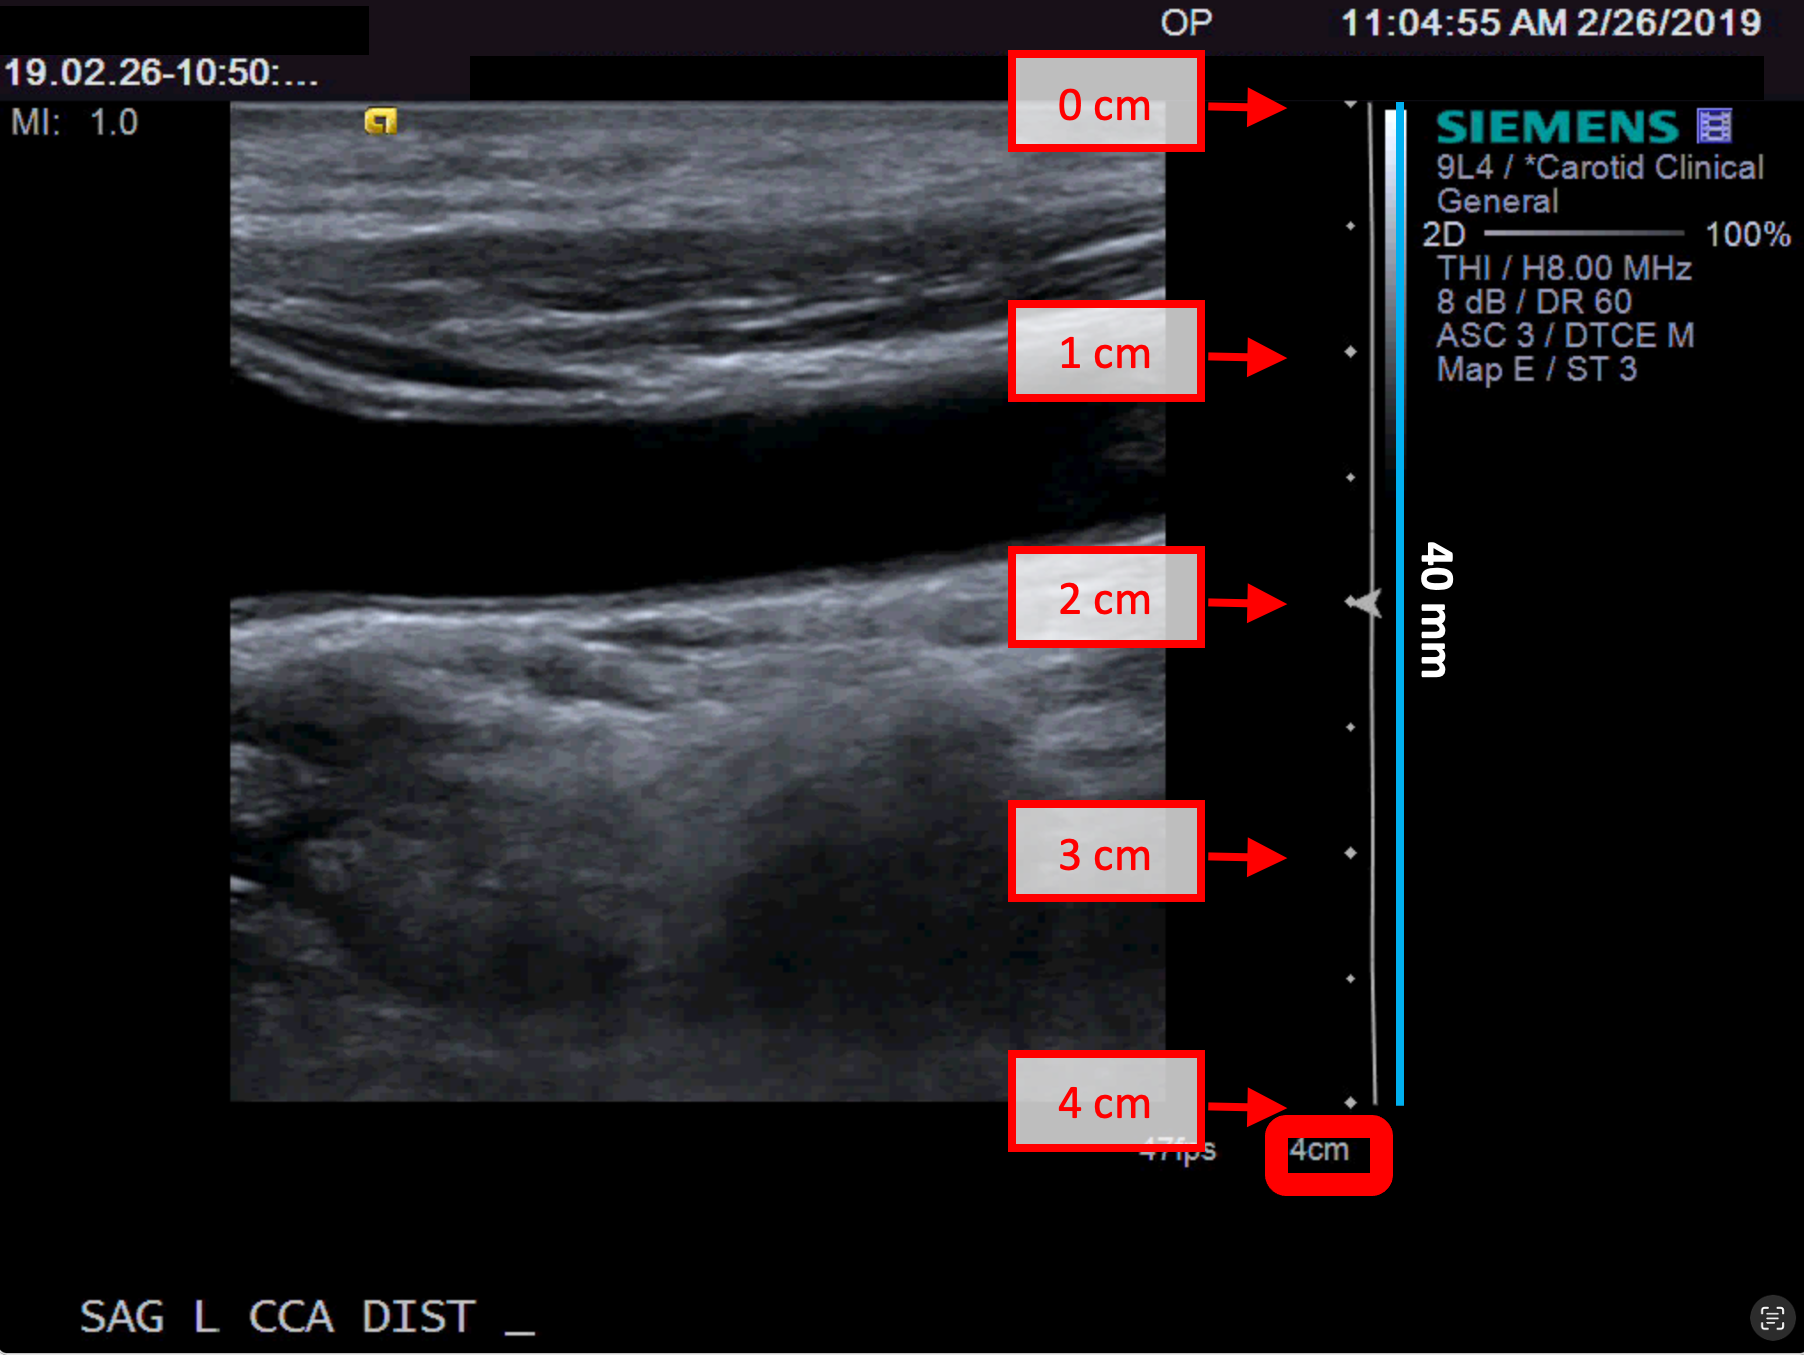

B-mode calibration examples

The following images show examples of calibrations of the b-mode image. Graphic items in red shows where you can find the information about the depth of the image in the ultrasound image.